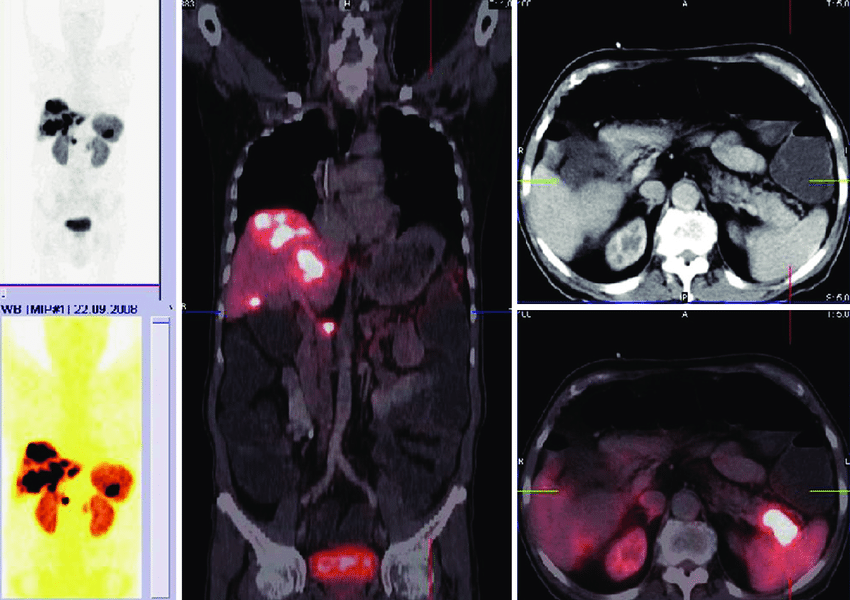

A vasoactive intestinal peptide (VIP) producing tumor give rise to a constellation of signs and syndrome known as Pancreatic cholera disease. It is also known as Verner-Morrison or WDHA syndrome. WDHA syndrome is an acronym for signs and symptoms produced as a result of VIPoma. It refers to Watery Diarrhea – Hypokalemia – Achlorhydria. Reference: https://en.wikipedia.org/wiki/VIPoma Image via: https://www.researchgate.net/figure/Patient-with-VIPoma-caused-by-pancreatic-neuroendocrine-tumor-in-the-pancreatic-tailand_fig6_233838802